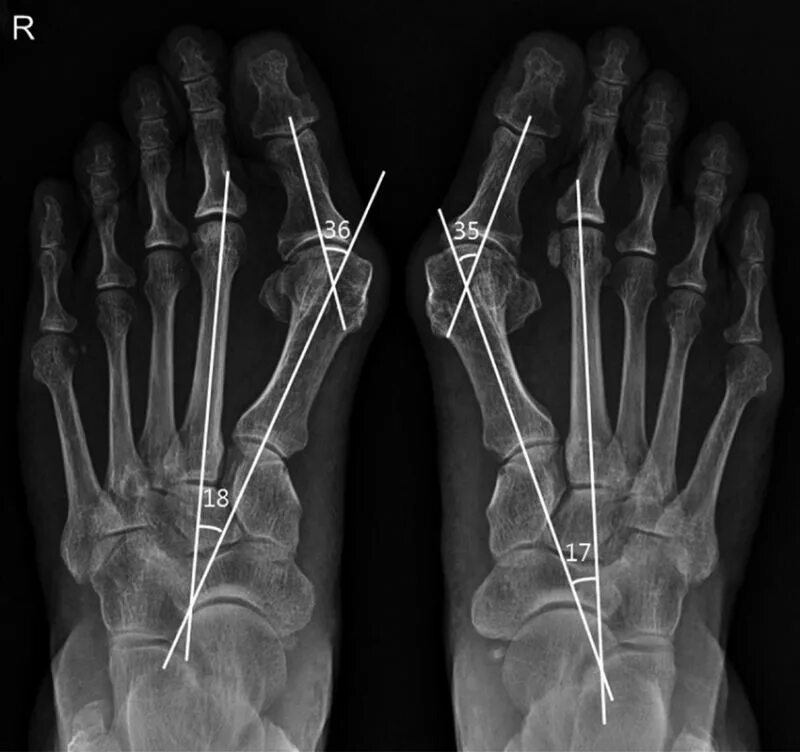

Угол пальца